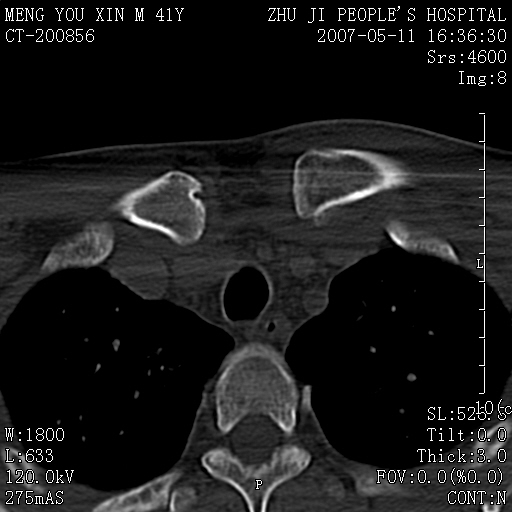

标题: CT8190:左锁骨胸骨端骨病,请会诊.

一周前左肩部酸痛,三天前颈部扭伤,后颈部摄片示颈椎病.现胸锁关节处肿痛明显.无发热.自诉三年前车祸安全气囊弹出.

左侧锁骨近端膨大,骨皮质中断,并见少许骨膜反应,内见破坏,边缘见筛孔征,无硬化.因此考虑骨巨细胞瘤可能.

双侧胸锁关节未见明显异常改变。

1,不支持结核,此例胸壁肿胀不明显,锁骨后方是局限性肿物而非脓肿,考虑为恶性肿瘤2,左侧锁骨近端膨大,骨皮质中断,并见少许骨膜反应,内见破坏,边缘见筛孔征,无硬化.因此考虑骨巨细胞瘤可能.